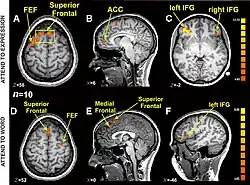

Cognitive and affective "paths": brain imaging data

-

Magnetic resonance imaging (MRI) of the brain is a technique used in personality research. Displayed here is a brain MRI of a normal subject.

Magnetic resonance imaging (MRI) of the brain is a technique used in personality research. Displayed here is a brain MRI of a normal subject. -

Research using functional magnetic resonance imaging of the brain suggests that cognitive and affective-expressive forms of communication and self-reflection have distinct neural bases.[50] Clinical findings have long suggested that verbalizations are often very incoherent when the individual is trying to put into words something deeply emotional.[51] Identification of words naming emotions (happy, neutral, sad) was found to be faster than identification of corresponding facial expressions. Recognition of face expressions was more difficult to suppress in favor of the recognition of words than vice versa, the two conditions presenting different patterns of brain activation. These experimental results suggest that reading and recognition of face expressions are stimulus-dependent and perhaps hierarchical behaviors, hence recruiting distinct regions of the medial prefrontal cortex.[48]

Research indicates that the representations of faces and objects in ventral temporal cortex are widely distributed and overlapping, face stimuli eliciting response patterns distinct from those elicited by object stimuli.[49]